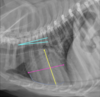

Which structures are outlined in this image?

A

light blue: ascending aorta

mint: main pulmonary artery

orange: right auricle

dark blue: right ventricle